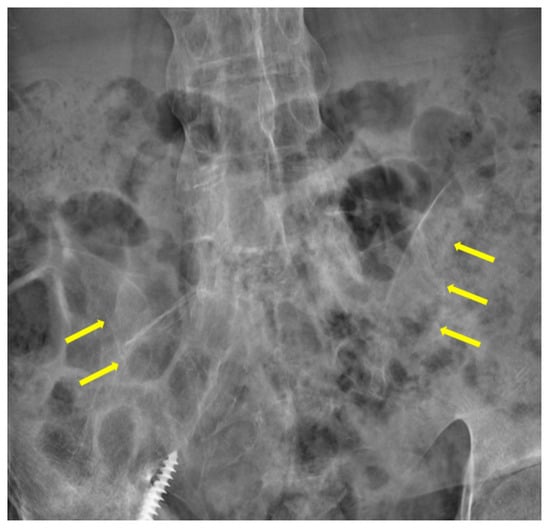

2. Case Presentation